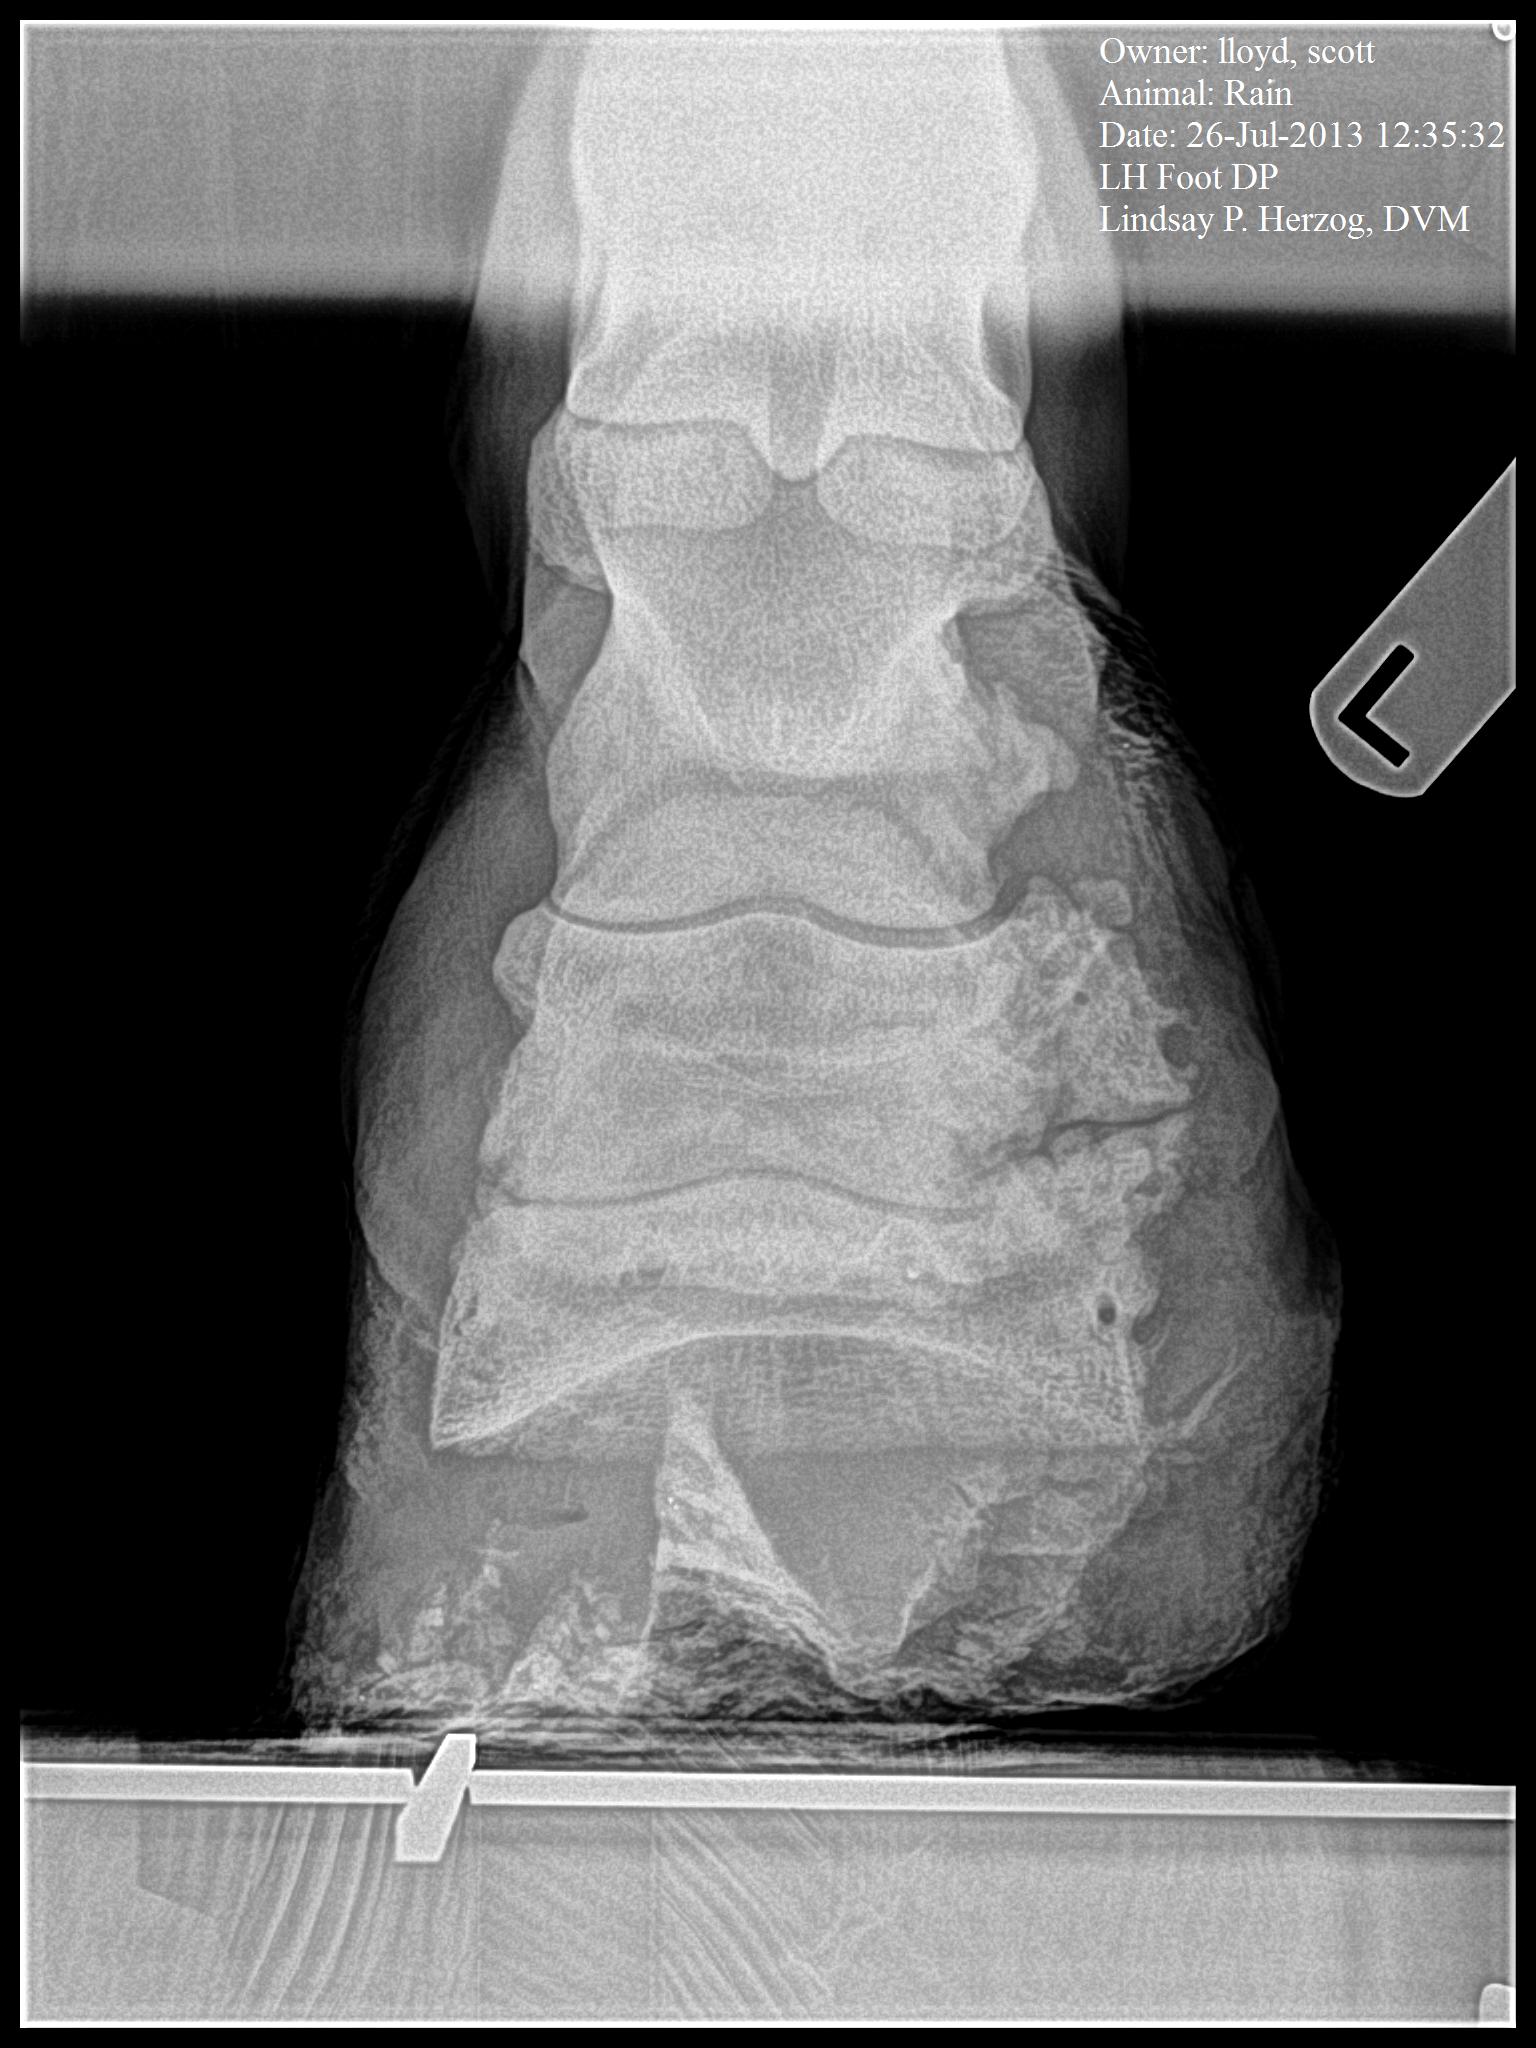

July 27, 2013

Ok, the xrays have been taken and the final determination has been made. Her wound

has completely healed, however there is some jagged bone growth. The determination has been made that she should have no problem carrying a foal, however the jagged bone growth would cause her pain if she were ridden, and possible damage tendons and cartiledge damage

If you look at the xray above, which is the uninjured hoof you will see the smooth edges on the bones and in contrast, the xray on the right, the injured hoof , you can see the rough and jagged boney growth on the outside.